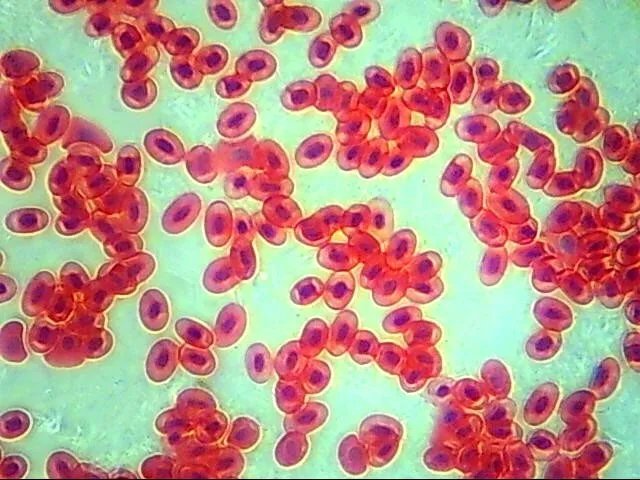

- Veterinary cytology with case record image capture

- Microbiology, parasitology, urinalysis with image archive

Which veterinary cytology / histology slides does this microscope read? Routine veterinary cytology smears (FNA, ear cytology, urine sediment), histopathology slides, fecal flotation / direct smear, urinalysis sediment, and hematology (Diff-Quik / Wright-Giemsa stained) workflow.